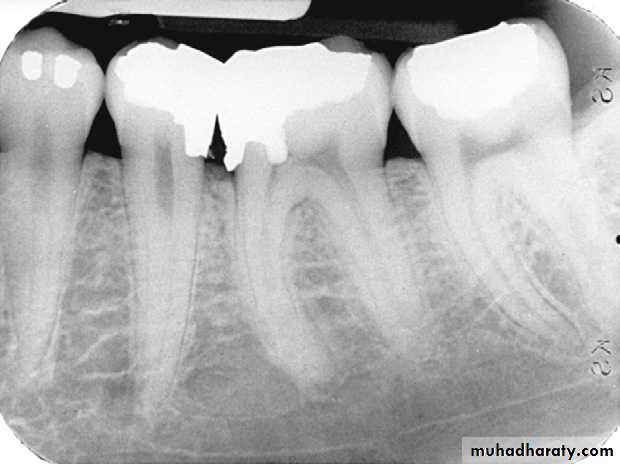

Defective Restorations

Amalgam overhang on the mesial surface of the mandibular first molar.

Ill-fitting restorations and open contacts between teeth contributing to the periodontal condition